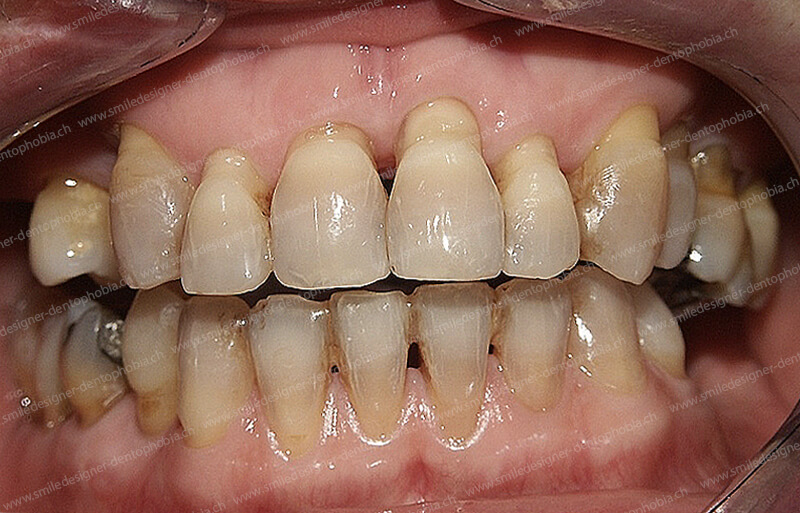

Cas clinique « DAMAGE CONTROL MCI » mandibulaire : Bridge implanto-porté avec extensions postérieures (ALL ON 6). Version définitive du bridge avec un cosmétique en céramique.